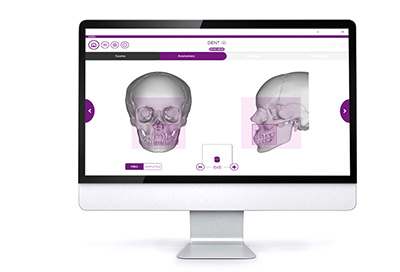

INTERFACE PC

La console multiplateforme vous permet d’accéder de manière simple et immédiate à toutes les fonctions de l’appareil. Une interface qui vous guide pas à pas dans toutes les phases, du choix au paramétrage de l’examen, avec le positionnement guidé du FOV : pour des examens plus faciles, plus rapides et plus efficaces.

FOV Interactive View

L’option FOV Interactive View, ellevous permet de redéfinir la dimension et la position dela zone de balayage directement sur le photogrammedu patient.